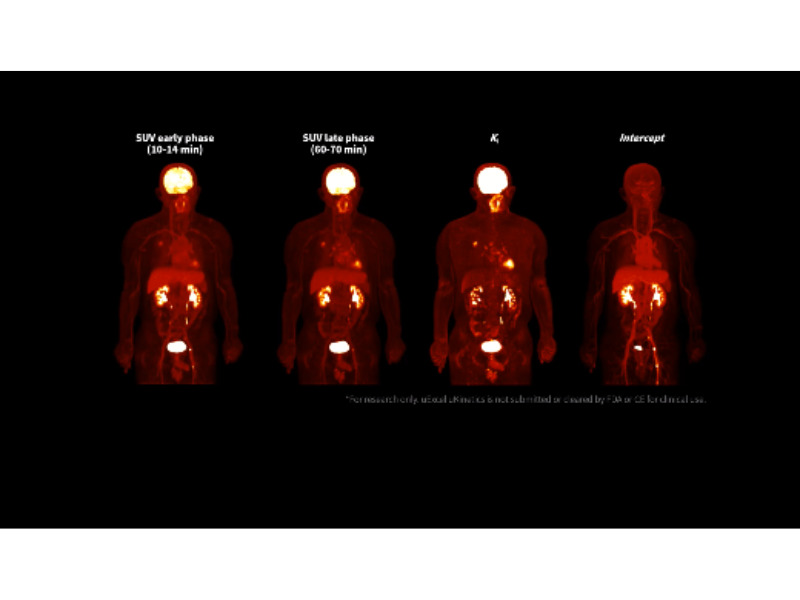

ki imaging reveals higher contrast within lung cancer on ukinetics.